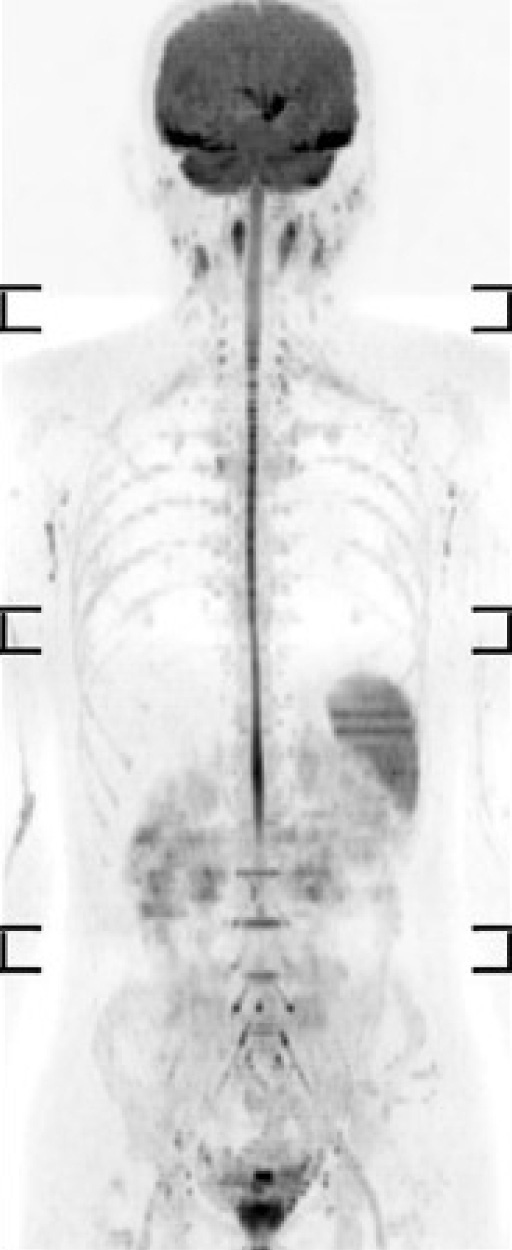

核医学検査

核医学検査とは

放射性医薬品とは

投与された放射性医薬品は、物理的減衰や排泄などにより、数時間~数日で体内から消失します。

また、副作用が少ないことが知られており、腎機能が低下している方や、造影剤アレルギーがある方にも受けて頂ける検査です。

当院の特色